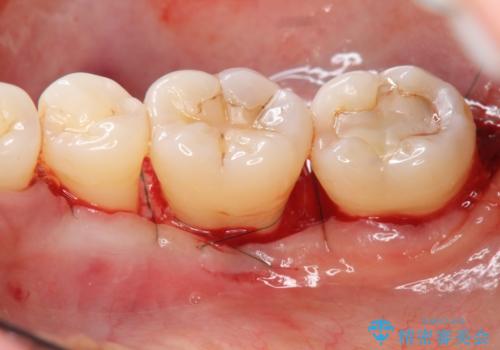

歯周病 再生治療で歯を残す

- 妊娠中に歯周病を指摘・自覚され、出産後に歯周病治療を希望され来院されました。

X線検査、歯周組織検査より歯の周囲の骨が溶ける歯周病であることがわかりました。

歯を抜かずに残せるよう、再生療法・歯周ポケット除去手術を計画します。

再生治療を行うことで、吸収した骨を再生し歯を保存できることがあります。